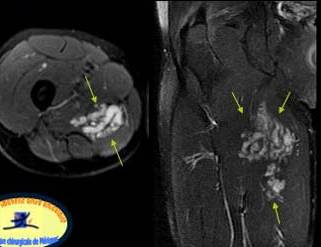

Echivalentul stadiului IV al lui Rodineau se caracterizeaza prin existenta unei rupturi sau unei dezinsertii musculo-aponevrotice complete cu,cel mai frecvent fascicol muscular retractat flotant intr-o cavitate hematica

Exista in aceste echivalente ale stadiului IV un caz particular, reprezentat de o ruptura osteotendinoasa (traumatismul spinei iliace antero-inferioare in leziunile dreptului femural la fotbalisti de exemplu

Stadiul IV Rodineau – ruptura la jonctiune mio tendinoasa

Muschi retractat flotant in colectie hematica

Echivalentul stadiului IV al lui Rodineau se caracterizeaza prin existenta unei rupturi sau unei dezinsertii musculo-aponevrotice complete cu,cel mai frecvent fascicol muscular retractat flotant intr-o cavitate hematica Exista in aceste echivalente ale stadiului IV un caz particular, reprezentat de o ruptura osteotendinoasa (traumatismul spinei iliace antero-inferioare in leziunile dreptului femural la fotbalisti de exemplu

Masa hiperecogena, difuz delimitata,

Compresibila, in adductor, avand o

structura tubulara

Corespondenta IRM